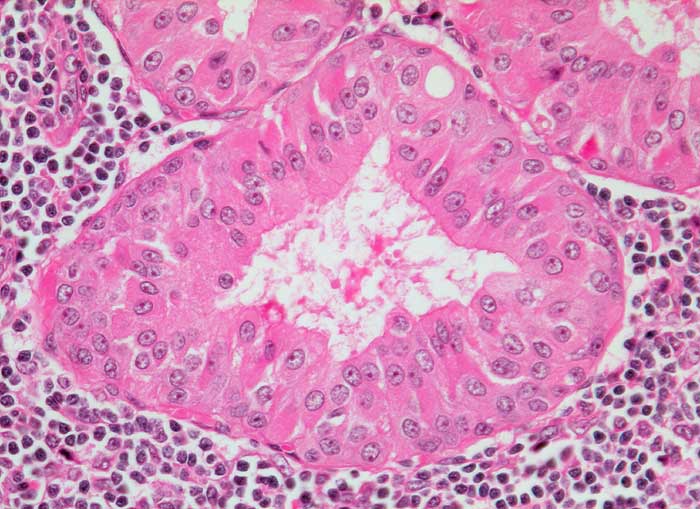

Warthin Tumor

Der Warthin Tumor ist ein zystisch papillärer Tumor mit lymphoidem Stroma und einem zweischichtigen onkozytären Epithel. Schleim- oder Becherzellen und metaplastisches Plattenepithel können vorkommen. Die diagnostischen Zellen werden oftmals verdünnt durch den Zysteninhalt, was in einer falsch negativen Punktion resultieren kann. Im Idealfall enthält das Punktat Onkozyten und Lymphozyten auf granulär zystischem Hintergrund. Oftmals fehlen aber die Onkozyten. Differentialdiagnostisch muss man in solchen Fällen an eine lymphoepitheliale (oder branchiogene) Zyste denken. Onkozyten kommen bei einer Vielzahl anderer Parotisläsionen vor: onkozytäre Metaplasie oder Hyperplasie, Sjögren Syndrom, Onkozytom, Mucoepidermoidkarzinom, Adenokarzinom, adenoidzystisches Karzinom.